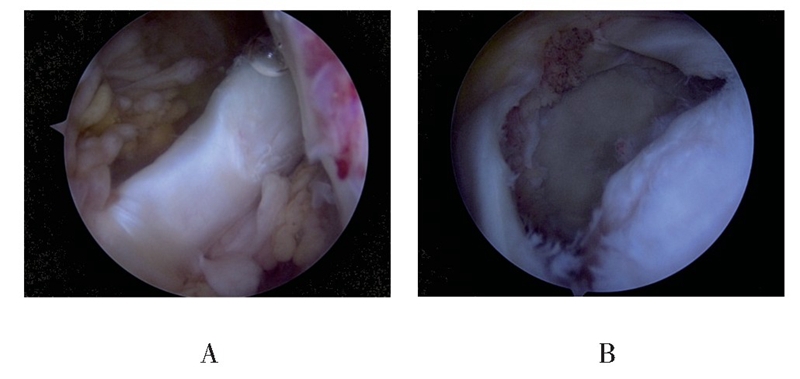

(1)首先外侧入路关节镜下观察评估肩袖撕裂及回缩情况,探查LHBT连续性及肌腱质量,术中确定肩袖为巨大撕裂,累及2根肌腱以上且冈上肌腱回缩明显,松解后仍难以拉回足印区或虽可拉回足印区,但张力较大,同时LHBT无明显撕裂或退变时,开始进行“Chinese Way”肩袖修补程序(见图1)。

图1 关节腔探查见LHBT连续性良好,无明显撕裂及严重退变(A);肩峰下间隙探查见后上方巨大肩袖撕裂,其中冈上肌腱回缩严重(B)

图2 骨性刨削清理冈上肌腱足印区(A),移位固定LHBT至冈上肌腱足印区(B)

图3 组织抓钳牵拉后方撕裂肩袖,判断肌腱张力及撕裂形态(A),在移位固定的LHBT后方植入2枚带线锚钉,连同缝合固定LHBT的缝线一起缝合冈下及部分冈上肌腱(B)

图4 修补完成后,根据远端LHBT肌腱质量选择切断或保留LHBT远端(A:LHBT远端已切断;B:LHBT远端保留)